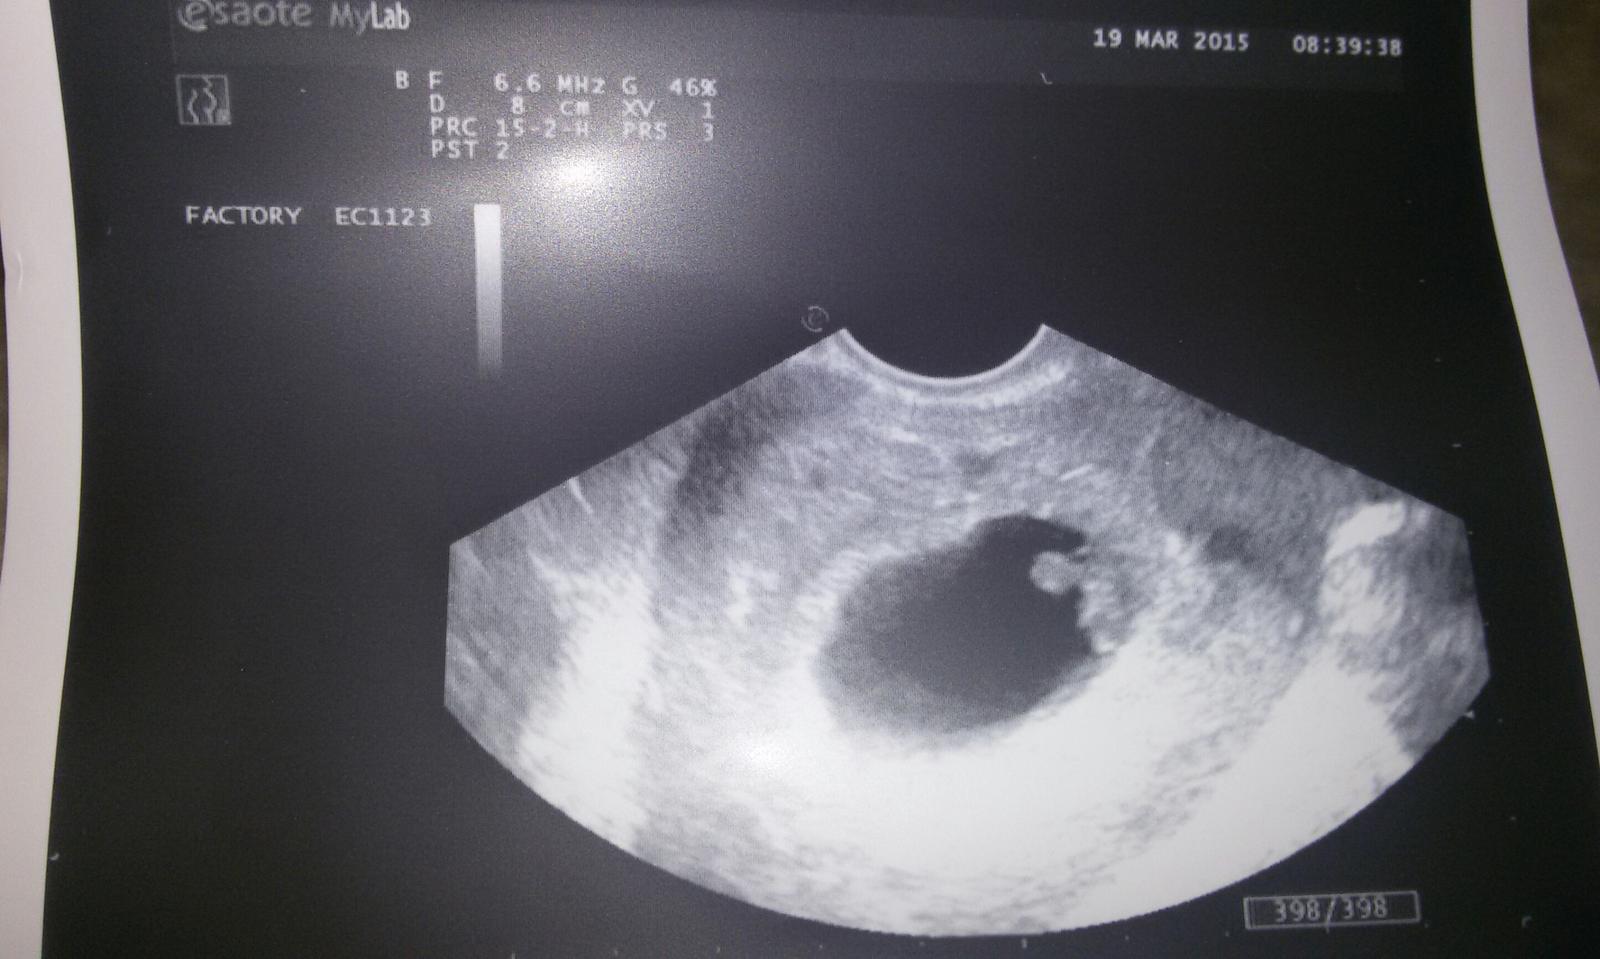

@marshmallow ved tam mas tu gulicku(zltkovy vacok) vedla drobca

@simusska ja nic nevidim moj ultrazvuk je ten druhy...ta baba co dala prva jej to pekne vidno